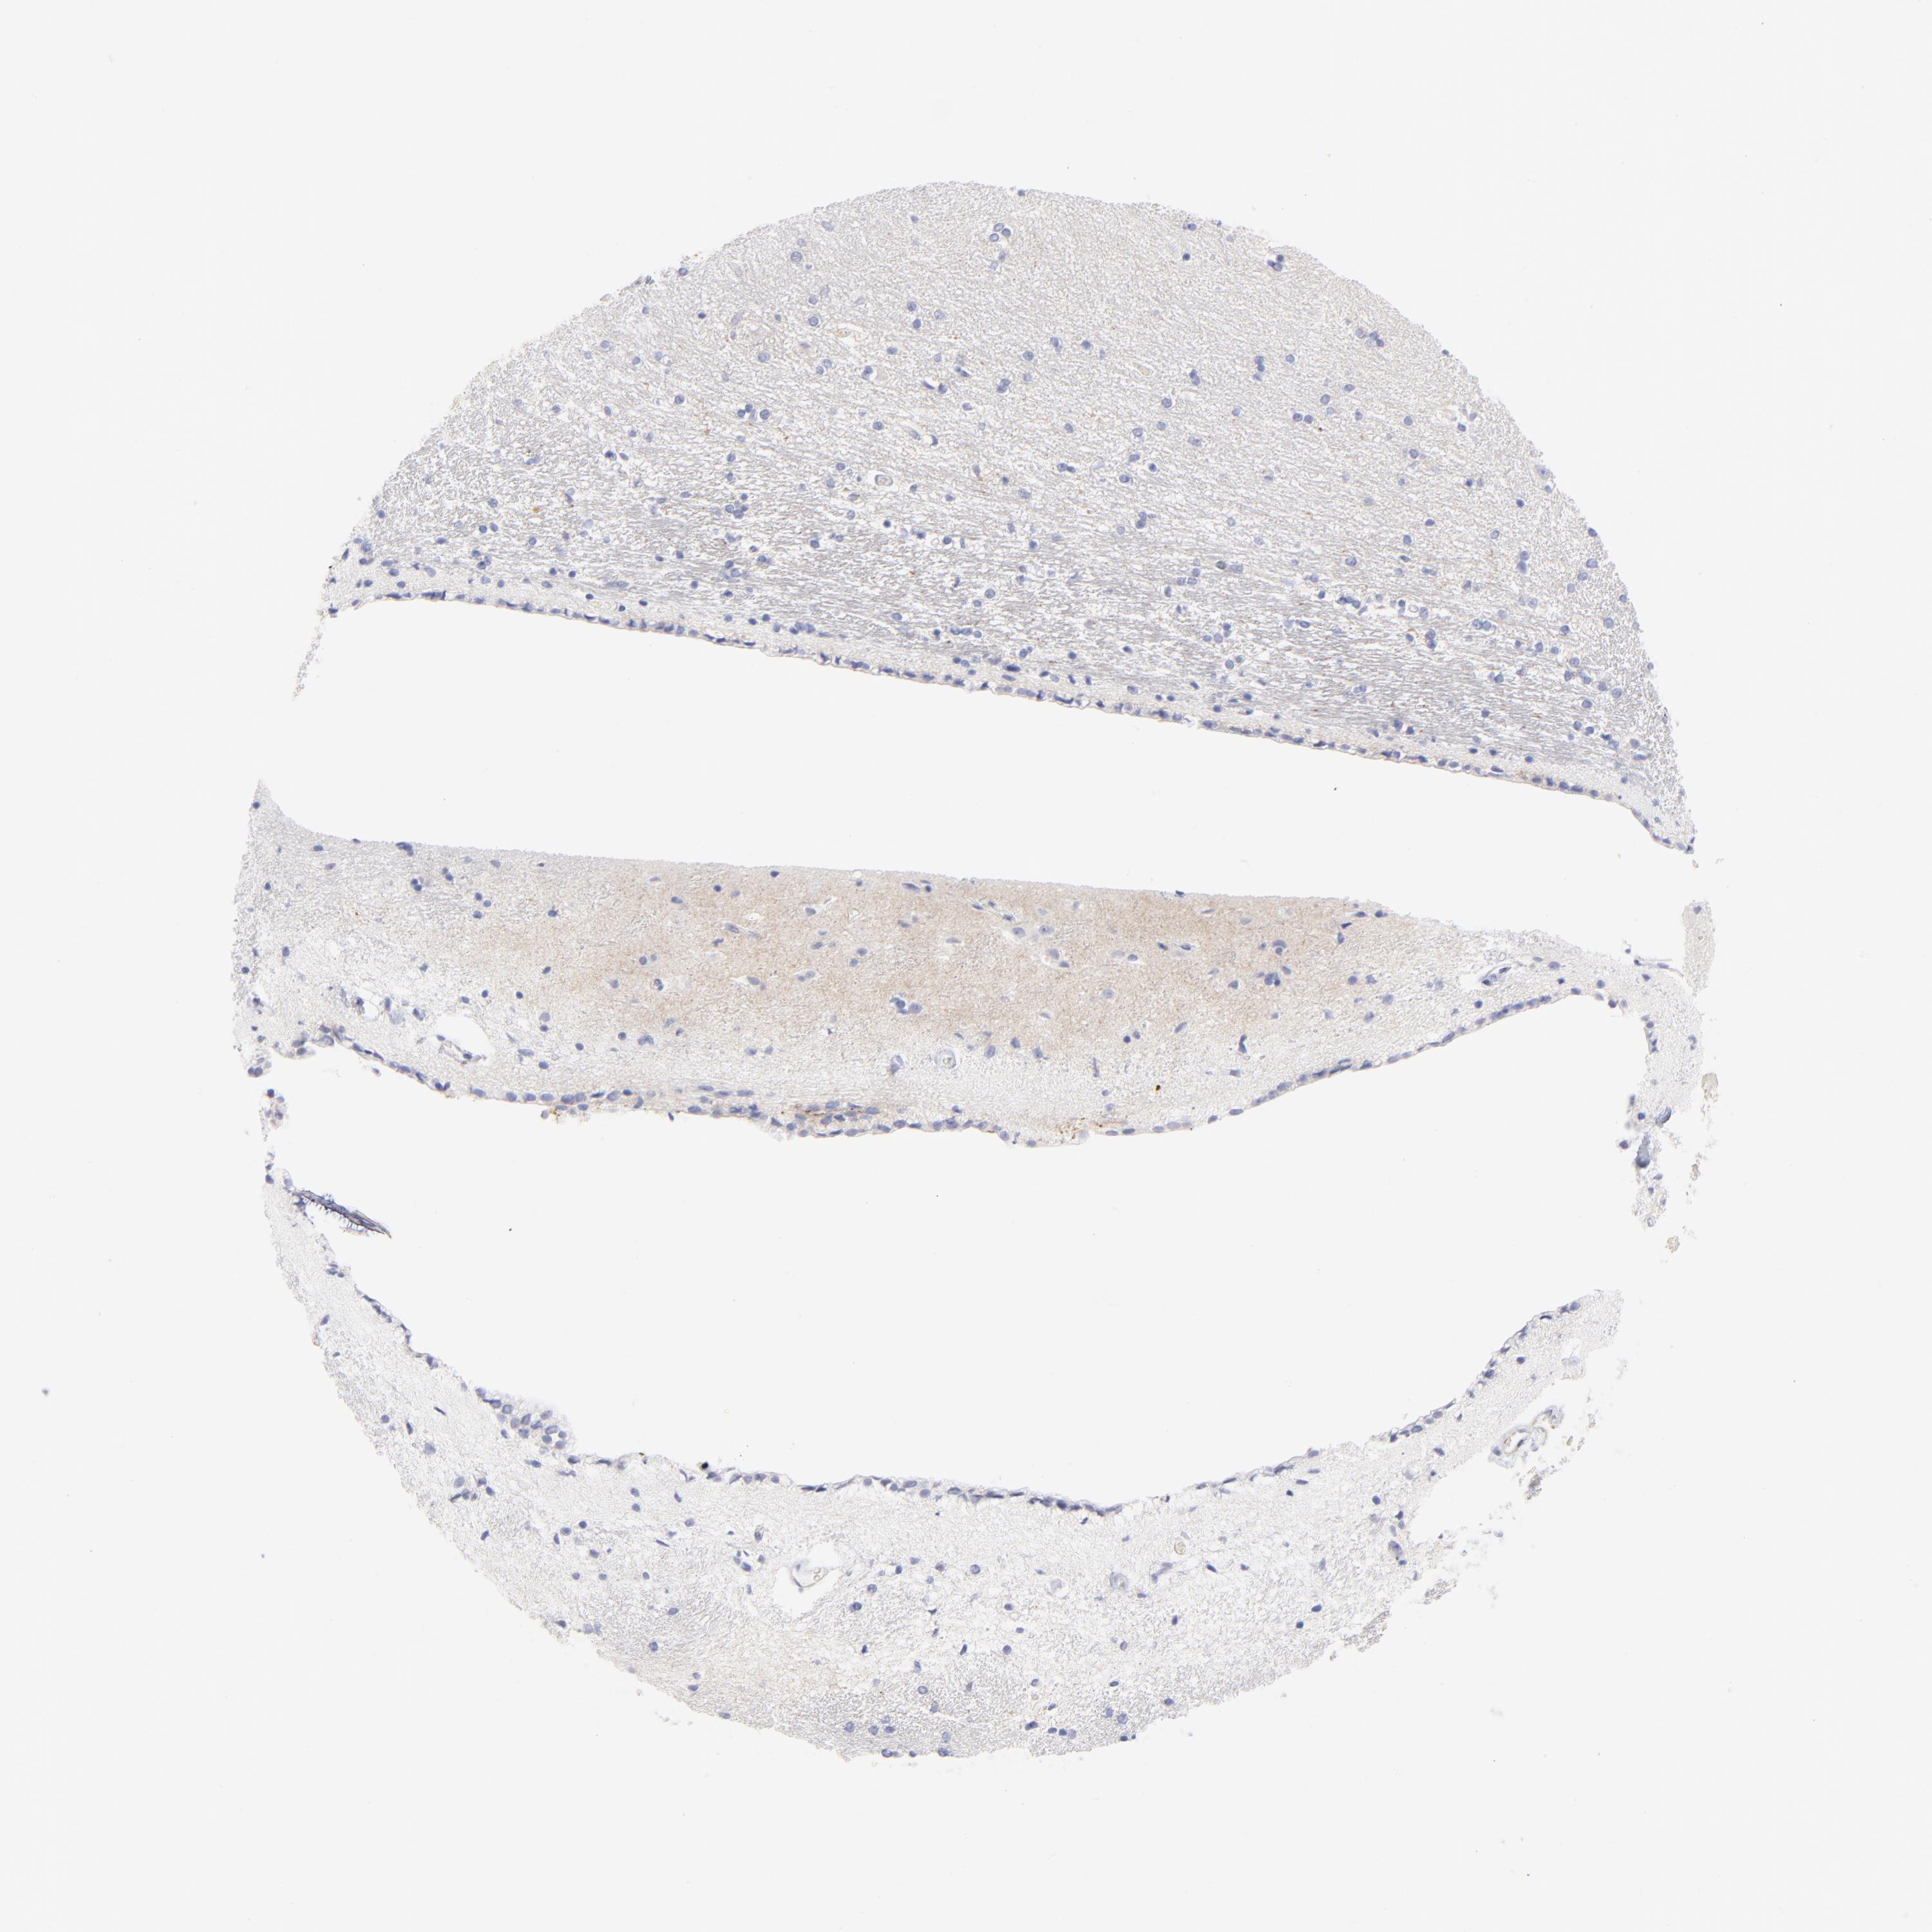

HIPPOCAMPUS - Antibody stainingi

Antibody staining in the annotated cell types in the current human tissue is reported as not detected, low, medium, or high, based on conventional immunohistochemistry profiling in selected tissues. This score is based on the combination of the staining intensity and fraction of stained cells.

Each image is clickable and will lead to virtual microscopy that enables deeper exploration of all samples and also displays staining intensity scores, fraction scores and subcellular localization as well as patient and tissue information for each sample.

Antibody HPA041264Antibody HPA041271Antibody CAB000002Antibody CAB003761Antibody CAB013531

Glial cells Not detectedNot detectedNot detectedNot detectedNot detected

Neuronal cells MediumNot detectedNot detectedNot detectedNot detected